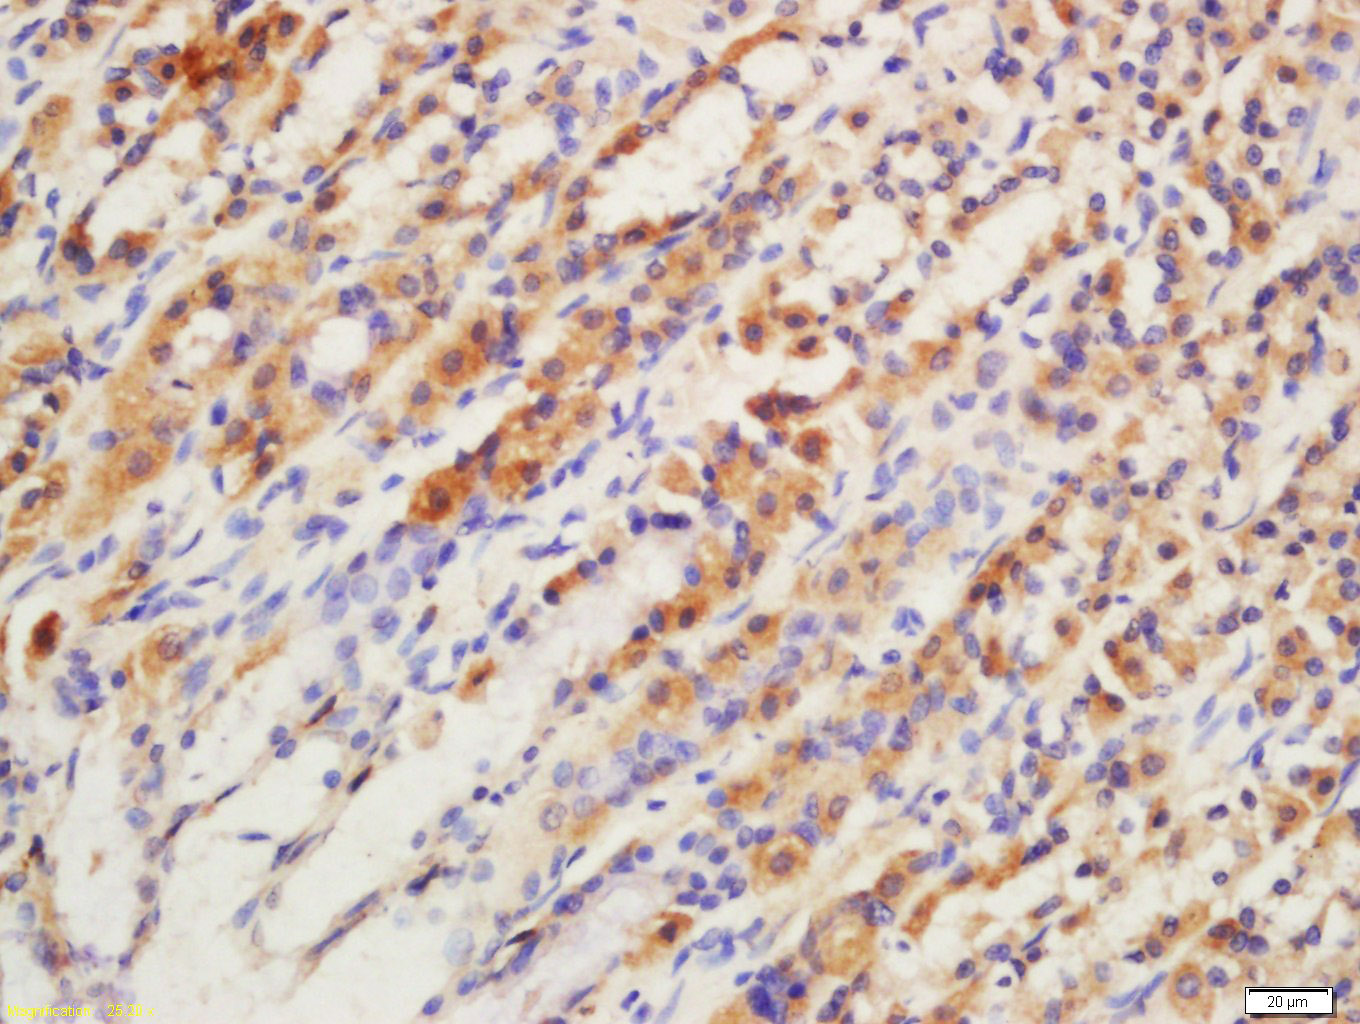

Tissue/cell: rat stomach tissue; Frozen section; Block endogenous peroxidase by 3% Hydrogen peroxide for 30min; Blocking buffer (normal goat serum,C-0005) at 37℃ for 20 min; Incubation: Anti-GPR15 Polyclonal Antibody, Unconjugated(bs-3699R) 1:200, overnight at 4°C, followed by conjugation to the secondary antibody(SP-0023) and DAB(C-0010) staining